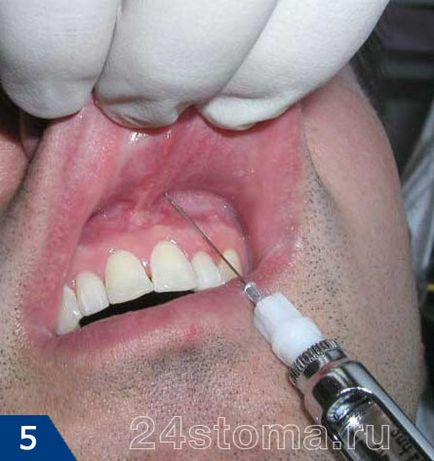

Знеболювання - для знеболювання застосовуються сучасні карпульних анестетики: Ультракаїн, септанест, Убістезін і ін. Тривалість їх дії становить від 40 хвилин до 3-х годин в залежності від способу анестезії.

Підготовка зуба до видалення за допомогою спеціального інструменту (гладилки) ясна відшаровується від зуба на глибину близько 0,5 см. Отслойка ясна дозволяє уникнути травмування ясенного краю і його розриву при накладенні щипців і витяганні зуба.